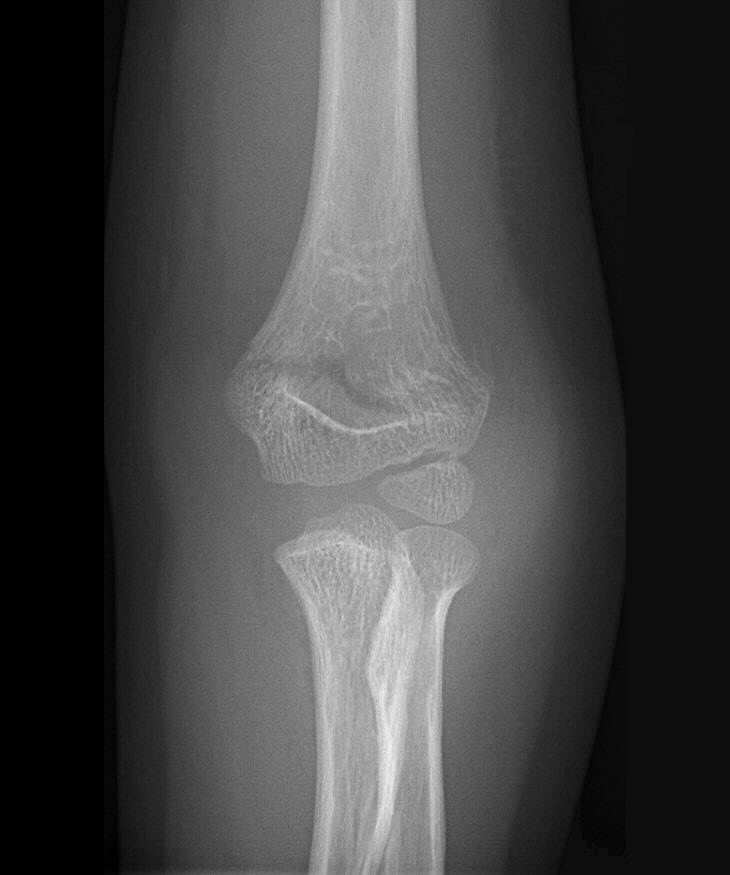

Fraktur på laterala humerusepikondylen, behandlades icke-kirurgiskt

Fraktur på mediala humerusepikondylen, behandlades icke-kirurgiskt